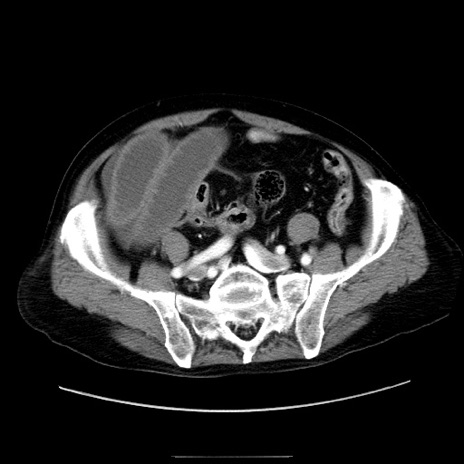

症例30(横断像)

【症例】80歳代男性

【主訴】臍周囲痛

【現病歴】約6時間前から臍下部痛が出現。次第に腹部膨隆・背部痛も生じてきたため来院。背部痛の場所は変化しない。

【身体所見】意識清明、BT 36.3℃、BP  131/87mmHg、P 87bpm、SpO2 100%(RA)、臍周囲自発痛・圧痛あり、反跳痛なし、自発痛部位に一致して板状硬あり、腹部膨隆、腸雑音減弱、CVA tenderness両側陰性。